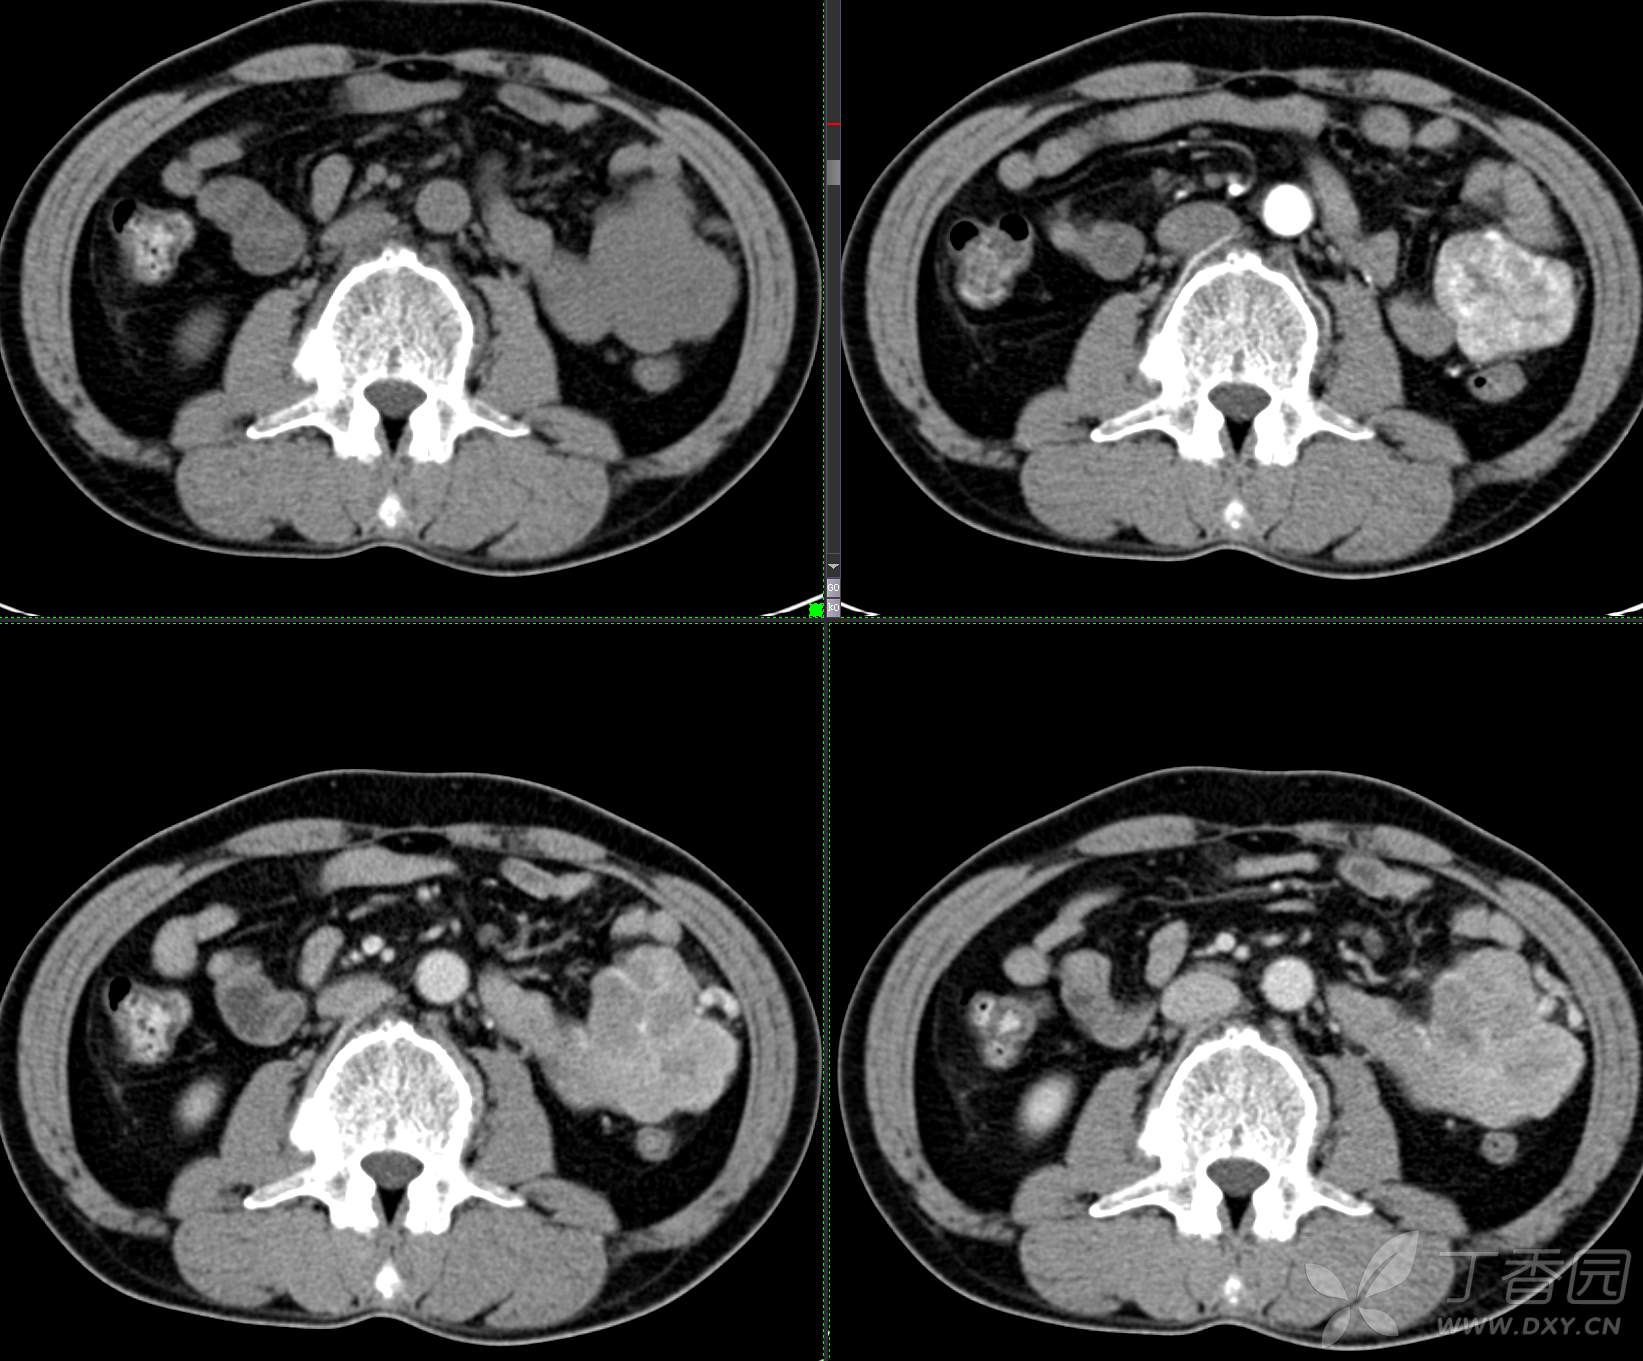

讨论:小肠病变,间质瘤?淋巴瘤?小肠腺癌?